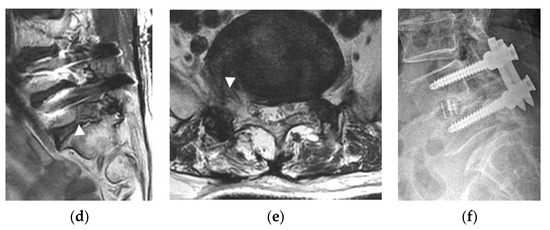

- Patients with L5 radiculopathy due to foraminal and extraforaminal stenosis at the L5-S1 level confirmed by MRI (Figure 1c,d).

- Patients with accompanying lateral recess stenosis at the same side with foraminal pathology, which simultaneously compress the L5 and S1 roots (Figure 1c,d).